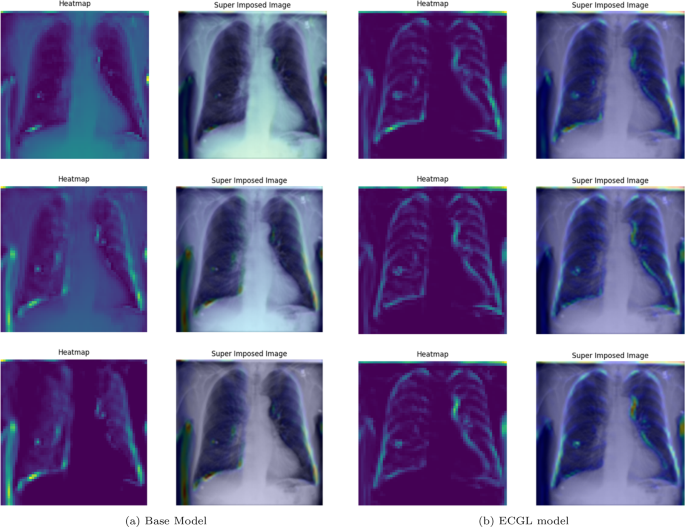

Figures 4 and 5 depict the GradCAM Heatmaps and Superimposed X-ray images of correctly and incorrectly predicted pneumonia instances, respectively. The areas in images that are highlighted in color represent the regions that the model deemed most important for its decision. Moreover, the overlay of the heatmaps on the original X-ray images provides valuable information, allowing us to assess whether the models are focusing on relevant features. The superimposed images refer to the original images combined with the heatmaps, providing a more comprehensible visual representation of the focused regions. The illustrated heatmaps depict three classification outputs corresponding to the labels 0, 1, and 2, arranged from top to bottom, respectively. Label 0 indicates “No Lung Opacity,” which refers to patients without diagnosed pneumonia. The other labels, 1 and 2, on the other hand, signify Lung Opacity and the presence of fuzzy white clouds in the lungs, associated with pneumonia.

GradCAM Heatmaps and superimposed images of the (a) base model and (b) ECGL model for correctly labeled instances. The illustrated heatmaps correspond to GradCAM visualizations for labels 0 (normal), 1 (pneumonia present), and 2 (pneumonia absent, abnormalities exist), arranged from top to bottom, respectively. (a) base Model. (b) ECGL model

Likewise, Figs. 6 and 7 compare the proposed ECGL model and the Base model in terms of explainability by using GradCAM heatmaps. While both models generally seem to be focusing on similar areas (central region) of the chest X-rays, the color intensity in the heatmaps and superimposed images obtained from the ECGL model clearly shows a greater emphasis on certain regions that are related to the respiratory system and pneumonia disease. As it can be seen in Fig. 4(a) and 4(b) (correctly labeled instances), the highlighted regions of the Base model are more blurred, hazy, and spread out across the image, suggesting that the model’s decisions are less interpretable and apparent to the experts. Whereas the proposed ECGL model presents more focused and localized highlighted regions, showing that the model is primarily relying on specific areas of the image, relating to the particular region attacked by the disease, to make its prediction. The ECGL model makes it easier to understand the model’s reasoning and therefore presents more explainability. In addition, the ECGL model produces a more concentrated heatmap, indicating more confidence in prediction.